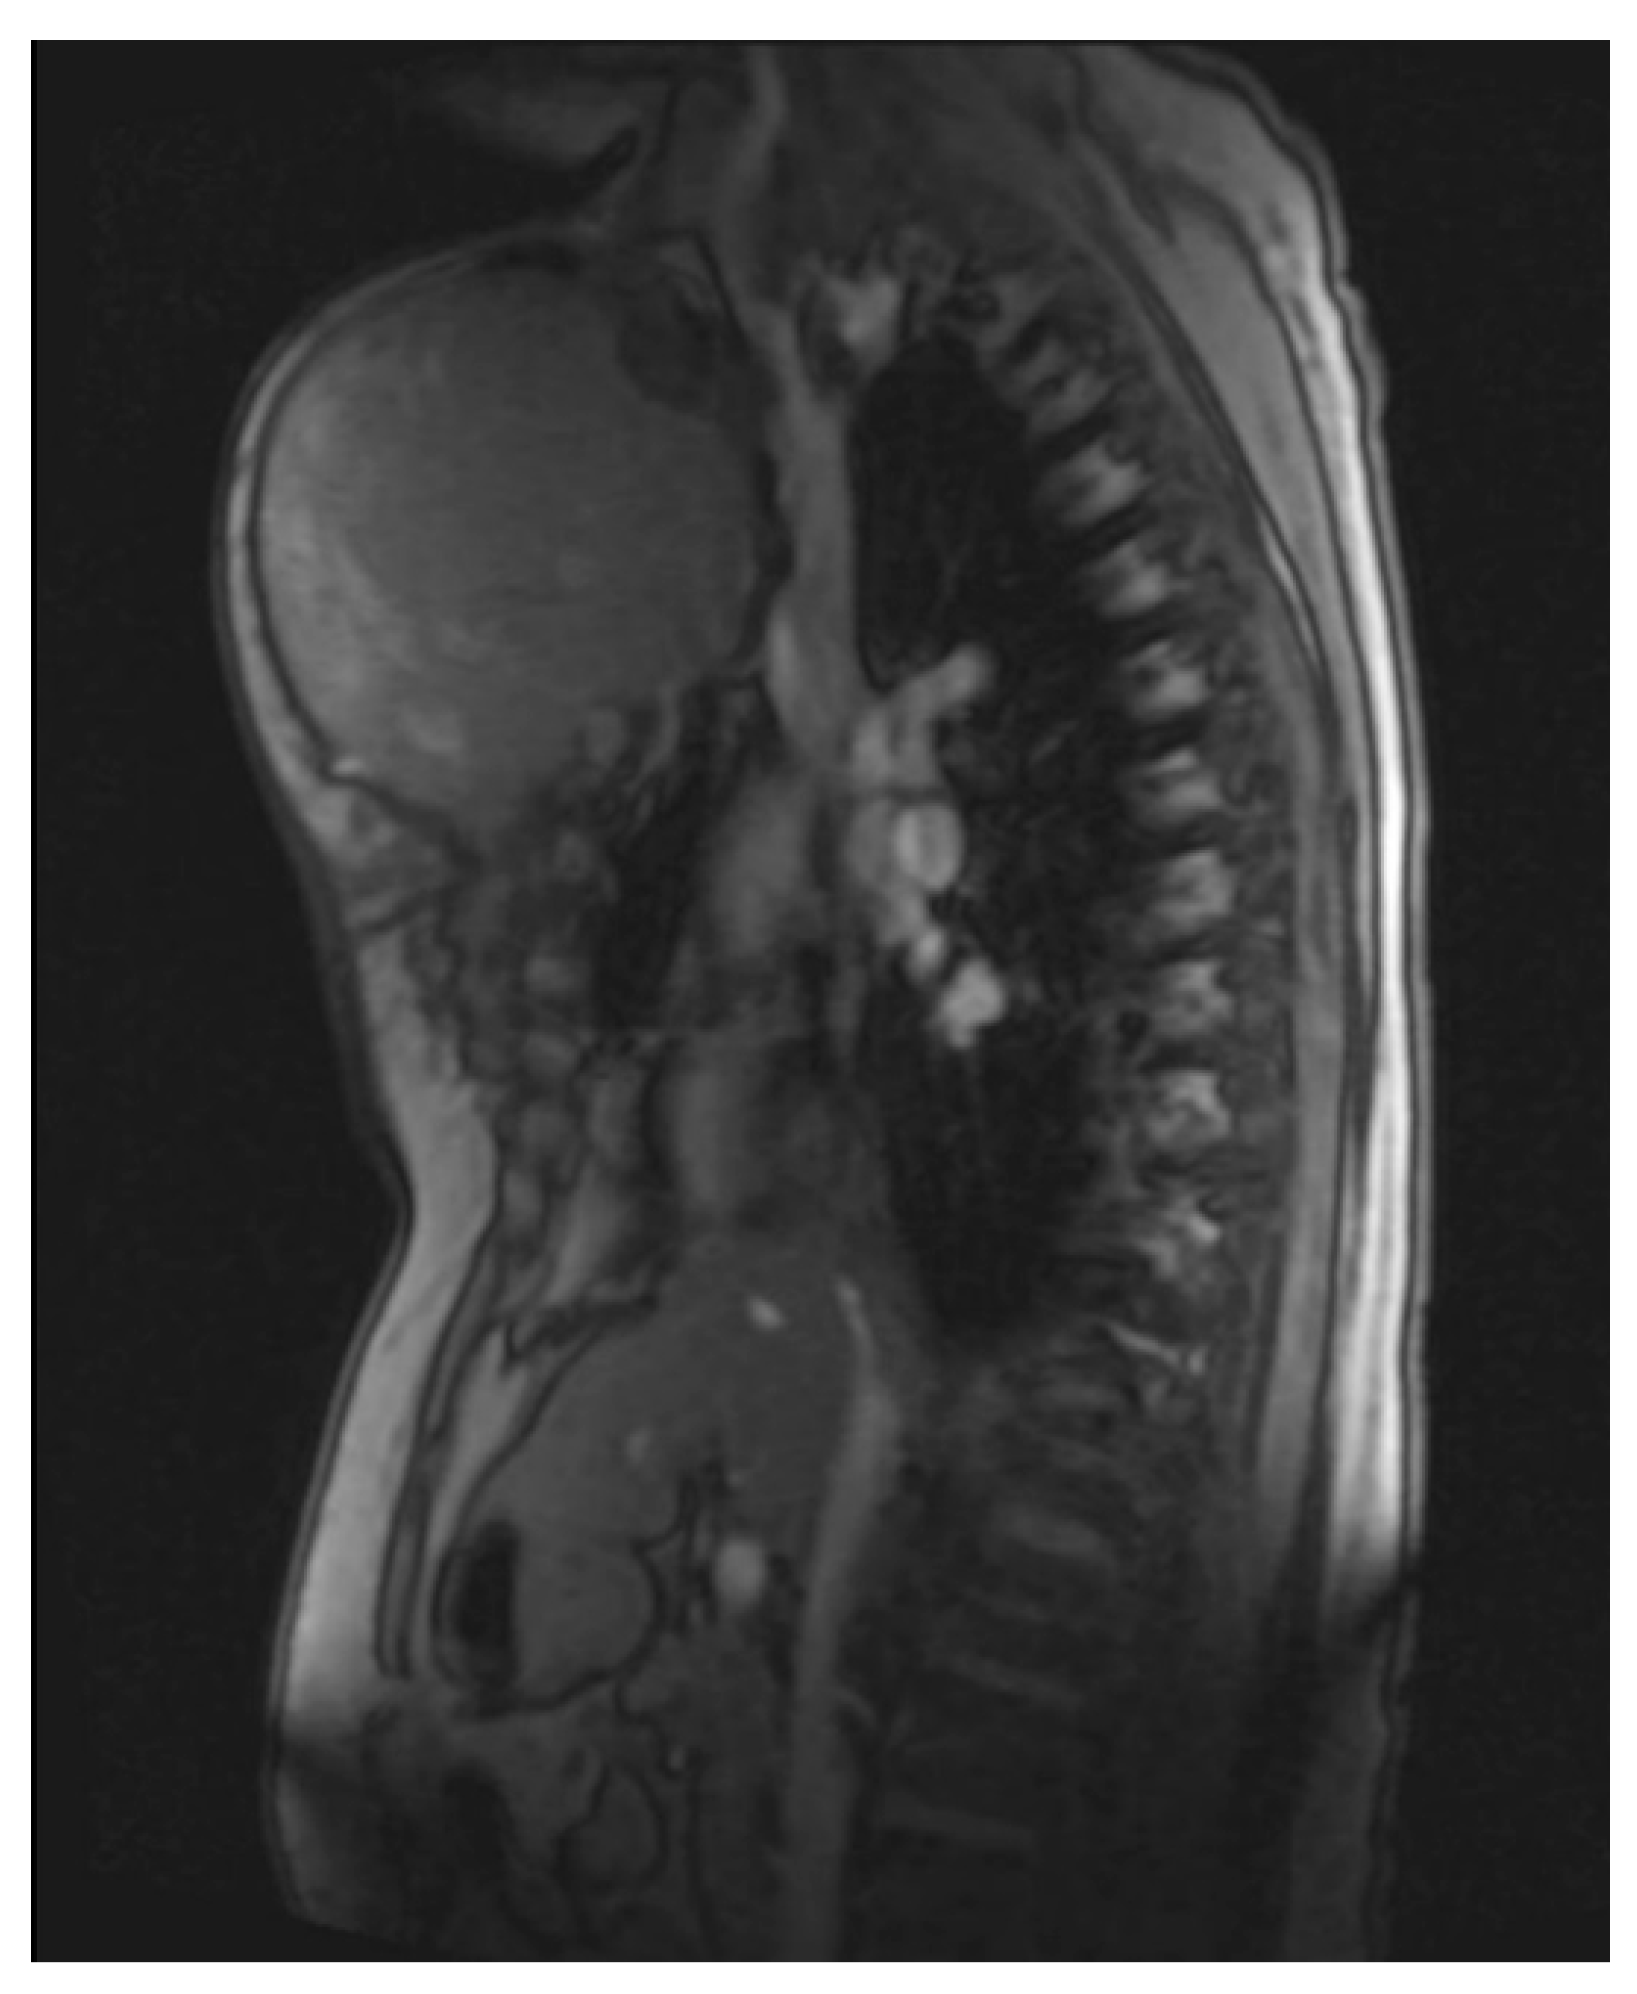

Figure 4.

Magnetic resonance imaging (MRI 2018) showing the large tumorous masses on the anterior thoracic wall, infiltration of the mediastinum per continuitatem, and contact with the aorta.

Figure 5.

Magnetic resonance imaging (MRI 2018) showing the bis soft tissue structure, partially calcified and infiltrating the sternum.